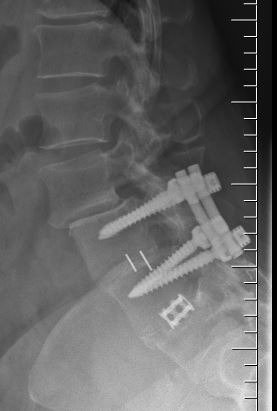

Another example is a young lady who had severe low back pain. Traditionally, fusion surgery through very large incisions would be required. With the new “percutaneous” technique of placement of pedicle screws, we were able to remove her disc through her abdomen and place screws through two small incisions in her back. She is now more than 80% improved.*

We have seen many such results. However, spinal surgery does carry Significant Risks and should not be taken lightly. Surgery, as minimal as it may be, should be utilized as the last option.